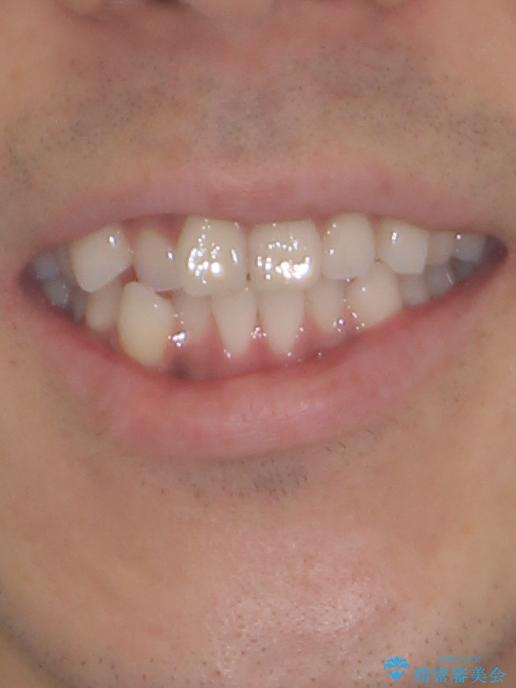

- 30代男性

- 上下顎歯列のデコボコを改善したいとのことで来院された患者様です。

自己管理の大変なインビザラインや、目立つ表側のワイヤー矯正は避けたいとのことで、

上顎だけ裏側装置のハーフリンガルにて矯正しました。